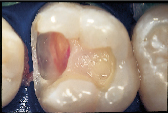

However, many of our restorative options are limited by patients financial situation. In cases where patients are forced to forego an ideal indirect restoration, a well-placed, less than ideal direct composite resin may be the best compromise treatment if they are seeking a non-metallic restoration (Figs. 4a and 4b). Consider the depth and width of the lesions of the three maxillary teeth in Fig. 4a. These teeth would be best restored with an indirect option subsequent to the appropriate gingival relocation. Nevertheless, for this patient who requested a tooth-coloured restoration, the challenge was met with innovative procedural manipulations and the diligent application of basic adhesive principles. Sometimes a compromise treatment is the best option in particular circumstances, as long as the decision is reached jointly by the dentist and patient and the latter is informed of all reasonable options.7 In this instance, the patient now has the opportunity to use an indirect approach in approximately eight years time when the restorative margins begin to break down. Without the direct intermediate treatment, the teeth may have been further structurally compromised by the expanding and leaking cariously undermined alloys. (It is not the authors intention to disparage the adhesive process but rather to put restorative expectations in perspective so that the appropriate level of clinical diligence can be maintained. Although improved placement techniques may enhance the performance of current posterior composite resins over their predecessors [ Fig. ], they should still be regarded as a compromised restorative option when applied to extensive lesions.)

| Figure 4a: For patients with limited finances, a well-placed, direct composite resin may be the best compromise treatment if they are seeking a non-metallic restoration | Figure 4b: Post-operative view of restored maxillary sextant. | Figure 5a: A direct composite resin was used for this maxillary first molar since the patient could not afford an indirect solution. | Figure 5b: Esthetics, function and form successfully restored. |